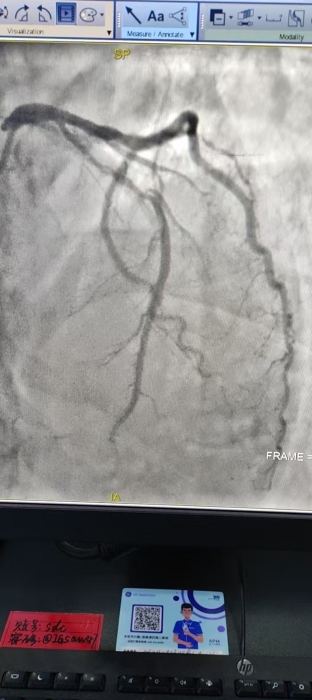

冠脉造影结果显示:患者左主干到前降支近中段重度钙化,伴70%~95%节段性狭窄,同时合并血栓,病变复杂、钙化严重,常规介入手术难度极大、风险极高。

△术前